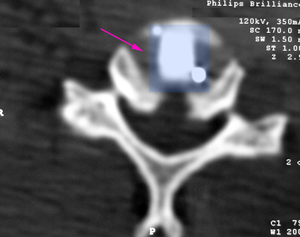

Πρόσθια αυχενική δισκεκτομή και σπονδυλοδεσία με κλωβό από PEEK (μπλέ) Α5-Α6.

Πρόσθια αυχενική δισκεκτομή και σπονδυλοδεσία με κλωβό από PEEK (μπλέ).